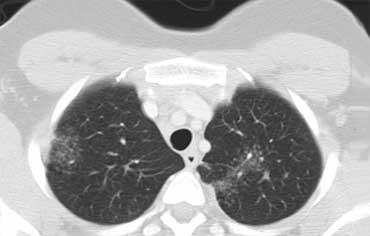

Bệnh nhân này nhập viện với triệu chứng khó thở cấp tính và phim X-quang ngực bình thường (không trình bày).

HRCT lúc nhập viện (trái) cho thấy các vùng kính mờ theo phân bố tiểu thùy.

HRCT kiểm tra mười ngày sau (phải) cho thấy các tổn thương đã thoái lui hoàn toàn mà không cần điều trị.

Các tổn thương được cho là do viêm phổi quá mẫn.